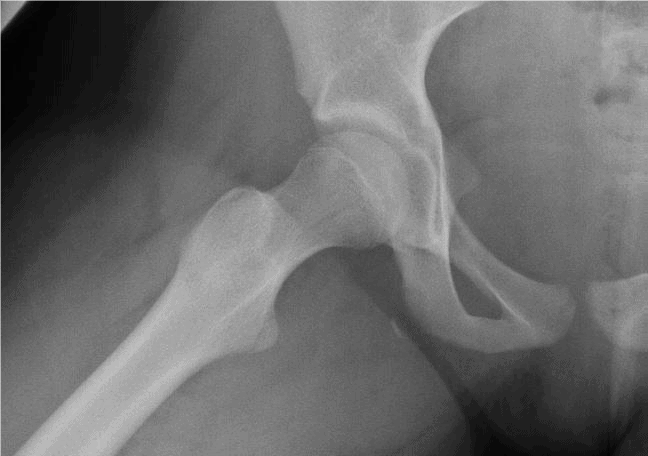

The patient is a 48-year-old woman who has had hip pain since joining her two sons and husband in a backyard touch football game yesterday afternoon. In particular, she describes planting her foot and trying so duck her older son’s grasp. She reports it is especially uncomfortable when driving or sitting at her desk at work.

View the images taken and consider what your next steps and a possible diagnosis would be.